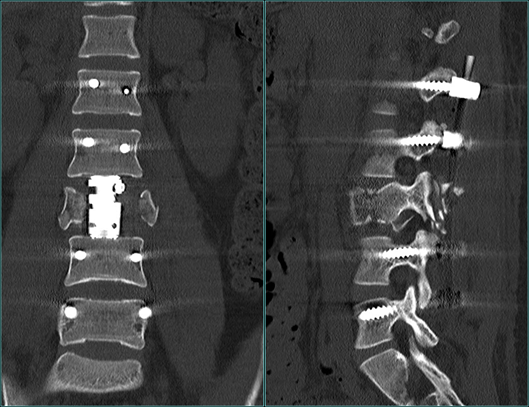

术后1周余复查腰椎X片、CT和MRI)

复查的影像检查结果也显示,小郑腰椎的植入物位置良好,脊髓和神经的压迫都消失了。此后,小郑还需要进行一系列的康复治疗,以获得更好的恢复。

在完成了必要的术前检查之后,张海龙主任经过全面的评估和慎重的考虑,为小郑进行了“腰椎后路减压+L1、L2、L4、L5椎弓根螺钉内固定+侧路人工椎体内固定术”。可伸缩的人工椎体在微创通道下放置到骨折节段,手术切口仅有5cm左右。